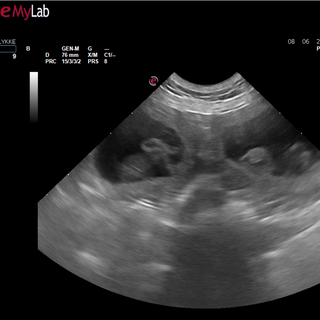

Den 8. juni ( på 29.dagen) var vi på Hinnerup Dyreklinik, hvor Kathrine kunne se mange fine babyer. Alle i samme størrelse og med fin hjertelyd.